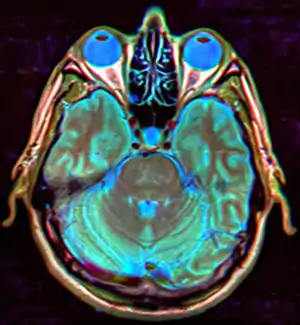

| Diagnostic method | MRI, CT scan[1] |